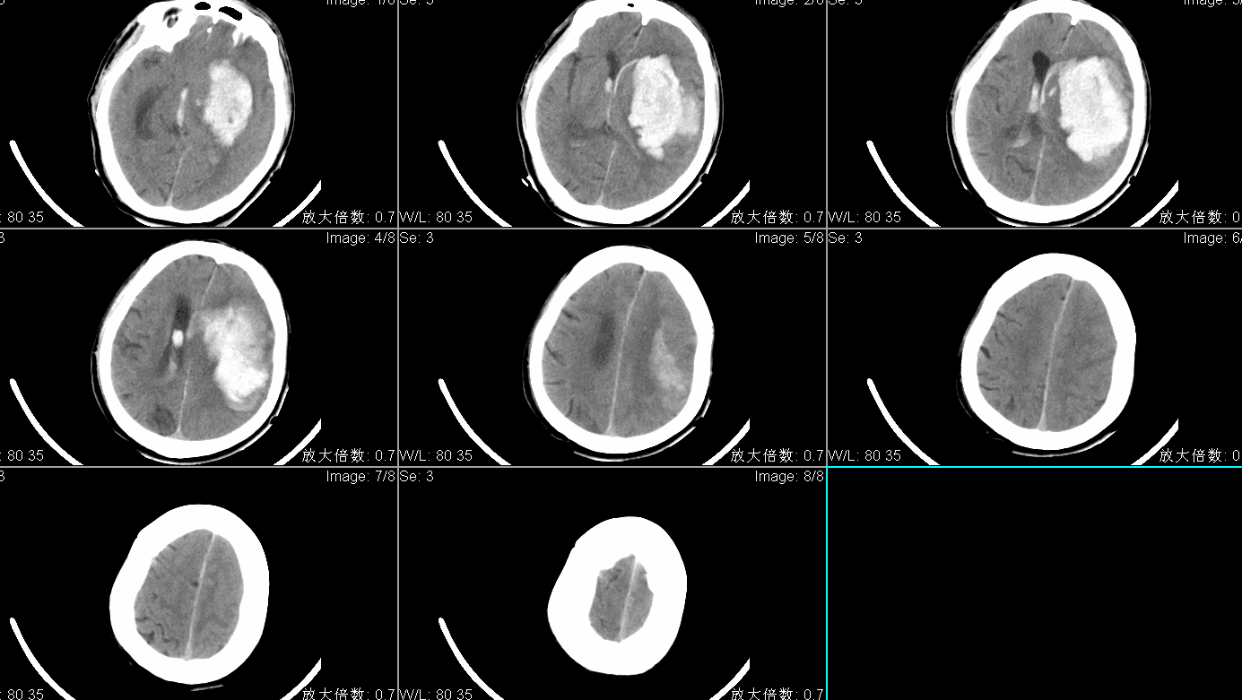

手术入路:神经内镜辅助经左额入路脑出血清除术。

术后CT复查左侧基底节区脑出血基本清除。